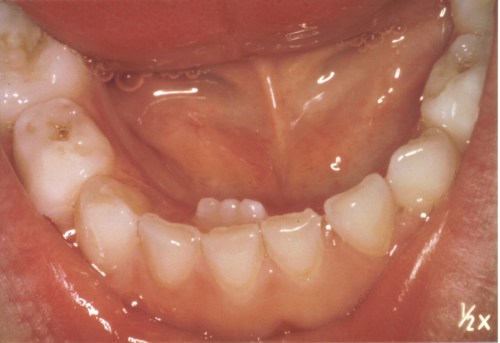

Det første billede ovenfor viser den første løse mælketand, der skal skiftes.